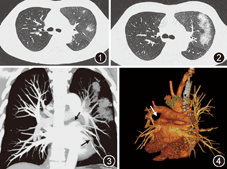

患者男,52岁。因"左侧胸痛1个月,咳嗽、间断咯血2周"于2014年8月21日入院。患者1个月前无明显诱因出现左侧胸部锐痛不适,胸痛在咳嗽或运动后明显,无胸闷、咳嗽、咳痰及发热等。X线胸片示双肺未见明显异常,心电图示"T波改变",心肌酶谱、D–二聚体均正常,给予"中药外敷"(具体不详)后胸痛有所缓解,但左侧胸痛始终存在,未进一步诊治。入院前2周患者出现小口咯血,伴轻咳,且左侧胸痛有所加重,2014年8月20日就诊呼吸科,胸部CT检查见左上肺散在斑片影及磨玻璃样改变,纵隔淋巴结无肿大(图1),拟以"左侧肺炎"收住院。患者自发病以来,无明显发热、盗汗,无明显胸闷、气喘,食欲睡眠可,大小便正常。既往有"高血压"病史7年,规则降压治疗,血压控制良好。有"阵发性房颤"病史10余年,近年来发作频繁,发作时头晕、胸闷不适,于2013年1月在我院心内科行导管射频消融(采用环肺静脉电隔离术),因房颤复发,于2014年1月再次行导管消融术(术式同前次),术后房颤消失,华法林钠常规抗凝治疗3个月后停药。否认急慢性传染病史及家族遗传病史。入院体检无阳性发现。入院后给予哌拉西林他唑巴坦、莫西沙星抗感染治疗,同时继续完善相关检查:血尿粪三大常规、ESR、C反应蛋白、D–二聚体、肿瘤标志物、肝肾功能、凝血功能及风湿免疫系统等检测均在正常范围。多次痰培养和痰抗酸杆菌检测阴性。心脏超声未见异常。经积极抗感染治疗患者左侧胸痛未见好转,仍小口咯血。2014年8月27日复查胸部CT可见左上肺病灶较1周前明显增多、增浓,部分病灶融合呈较大范围之团片状,左下肺亦出现少量斑片状影,左侧胸腔少量积液(图2)。复查血常规、C反应蛋白仍正常,遂停止抗感染治疗。为排除肺结核,继续查痰抗酸杆菌仍阴性;为排除真菌感染,查1,3–β–D葡聚糖(G试验)、乳胶凝集试验阴性;为排除血管炎,复查抗中性粒细胞胞质抗体(ANCA)、抗肾小球基底膜抗体阴性;为排除肺动脉栓塞,复查D–二聚体正常、下肢静脉多普勒超声检查未见血栓形成、心脏超声肺动脉压无增高。考虑患者先后有2次环肺静脉电隔离治疗房颤病史,最后一次导管消融在症状出现前6个月,此次发病是否与导管消融相关?是否存在术后肺静脉狭窄而致肺淤血?2014年9月1日行多层螺旋CT肺血管造影:肺动静脉双期相扫描,肺动脉相未见异常,肺静脉相示左肺上叶静脉闭塞(左上肺静脉造影剂不能充盈),左下肺静脉分支轻度狭窄,右侧上、下肺静脉充盈良好(图3,图4)。"医源性肺静脉狭窄"的诊断可以确立。因房颤导管消融术后"迟发性肺静脉狭窄"相对少见,多数学者认为其尚缺乏理想的治疗手段。现有的治疗方法包括介入治疗和外科手术均存在一定的缺陷和风险,且患者胸痛、咯血无明显加重,经慎重考虑后决定暂不行介入和手术治疗。考虑狭窄或闭塞的肺静脉内有血栓形成可能,给予华法林钠抗凝治疗。观察、治疗1个月,患者仍有左胸隐痛,时有痰血,复查胸部CT左上肺病灶较前部分吸收,左下肺斑片影及左侧少量胸腔积液消失。目前仍继续抗凝治疗,动态随访观察。

环肺静脉电隔离术已经成为当今治疗房颤的主要方法,肺静脉狭窄是该治疗最主要的并发症之一[1,2]。肺静脉狭窄在术后第1周进展最快;其次是术后3个月内;术后半年出现的迟发性肺静脉狭窄较少见[3,4,5,6]。临床极易漏诊、误诊。本例患者以胸痛、咯血为首发症状,胸部影像学表现左上肺大片斑片影及磨玻璃影,就诊于呼吸科,临床医生首先考虑:(1)感染性疾病;(2)常见疾病;(3)本科疾病。初诊"左上肺炎",抗感染治疗1周症状未见缓解,左上肺渗出性病灶反而增多、增浓。进一步详询病史,患者因房颤曾2次施行导管消融术,最后一次在症状出现前6个月,左肺病灶是否与此有关?入院第10天行多层螺旋CT肺血管造影检查明确诊断"左肺静脉狭窄"。该诊断足以解释患者的所有症状及影像学表现和治疗中的困惑:左上肺斑片影及磨玻璃影为左上肺静脉闭塞后肺淤血所致,抗感染治疗无效。本例患者的诊断经验和教训是:(1)完整的病史采集给正确诊断提供了重要线索;(2)正确的诊断应能解释患者的所有临床表现及治疗反应;(3)选择合适的检查方法是确立诊断的关键之一。

导管消融肺静脉狭窄的机制与诊断:因阵发性房颤的发生均为局灶性快速激动机制,绝大多数存在于肺静脉,故肺静脉消融成为当前治疗房颤的重要方法,导管消融后肺静脉狭窄发生的两个关键因素为高温度(>50 ℃)消融和消融部位过深[7]。也有文献报道狭窄出现与消融的次数有一定关系,Packer等[8]报道了23例严重的肺静脉狭窄病例,其中52%的患者因房颤复发进行了2次消融,22%的患者进行了3次消融,而本例患者恰恰也因房颤行2次射频消融。早期消融的病例,肺静脉狭窄的发生率可高达28%,随着肺静脉电隔离技术方法学的成熟和经验的增加,近年来肺静脉狭窄的发生率已明显下降,一般为5%~8%[5],但随之而来也导致了临床医生对其重视度下降及认识不足。诊断肺静脉狭窄的方法有螺旋增强CT、MRI造影及肺部同位素扫描等无创性检查,金标准是肺静脉造影,但属于创伤性检查,若患者准备行介入治疗则可选用。CT肺血管造影不但可用于诊断肺动脉疾病,延迟扫描后还可以清楚显示各肺静脉,是评价和诊断肺静脉狭窄及其严重程度的重要无创性检查方法[9]